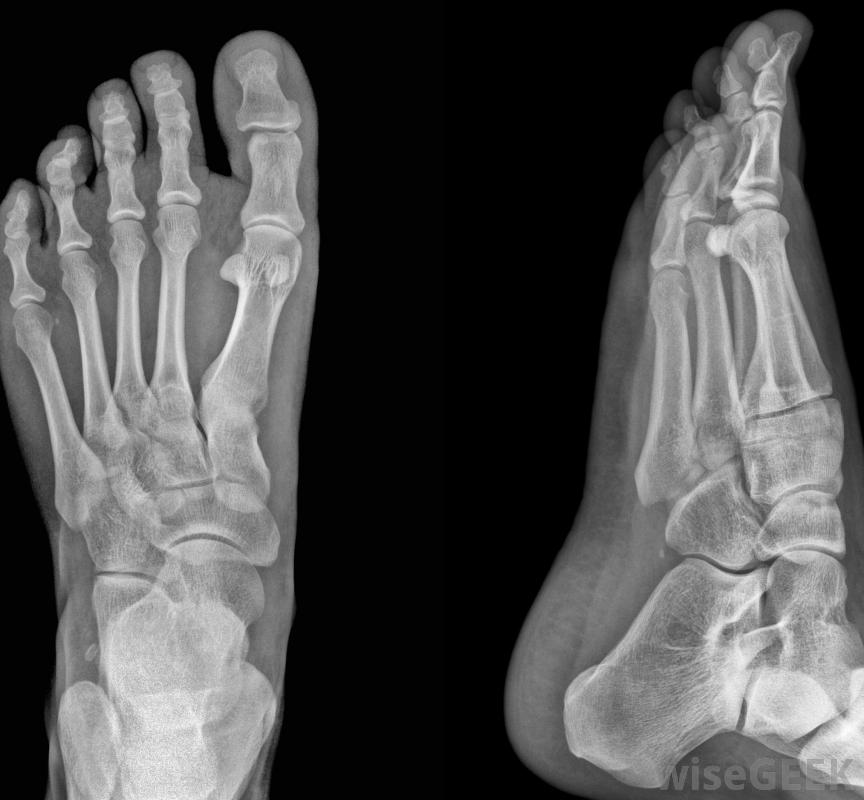

物理治疗师经常研究步态,以便发现患者的骨骼问题